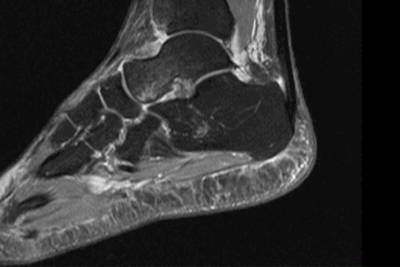

На серии МРТ правого голеностопного сустава соотношения в суставе не нарушены.

Определяется выраженный отек подкожной жировой клетчатки латеральных отделов.

В полости голеностопного и подтаранного суставов отмечается скопление жидкости. Синовиальная оболочка достоверно не изменена.

Кости, образующие голеностопный сустав, имеют обычную конфигурацию и расположены правильно. Выемка, образуемая лодыжками, развита хорошо. Патологических сигналов от лодыжек не выявлено. В краевых верхненаружных отделах блока таранной кости отмечаются локальные участки неинтенсивного, вероятно контузионного, трабекулярного отека.

Дельтовидная связка типичной структуры, без признаков нарушения целостности поверхностной и глубокой порций связки. Сухожилия длинного сгибателя большого пальца, длинного сгибателей пальцев, задней большеберцовой мышцы однородной структуры. Структура сухожилий малоберцовых мышц однородная. Передняя и задняя нижние межберцовые связки сохранены, межберцовый синдесмоз равномерный на всем протяжении. Передняя таранно-малоберцовая связка неоднородной структуры, прослеживаются немногочисленные волокна с признаками натяжения. Задняя таранно-малоберцовая связка определяется на всем протяжении, сигнал от связки неоднородный, отмечается продольное разволокнение связки, общее натяжение связки сохранено. Пяточно-малоберцовая связка прослеживается на всем протяжении, неоднородной структуры за счет отека и частичного повреждения волокон. Ахиллово сухожилие имеет нормальную толщину, ход и характеристики сигнала. Окружающая сухожилие жировая ткань не изменена. Сухожилия и подошвенный апоневроз без особенностей.

Суставные хрящи голеностопного и подтаранного суставов не истончены. Суставные полости правого голеностопного и подтаранного суставов не сужены.

Заключение: МР-признаки разрыва передней таранно-малоберцовой связки; повреждения передней таранно-малоберцовой и частичного повреждения пяточно-малоберцовой связок. Синовит.